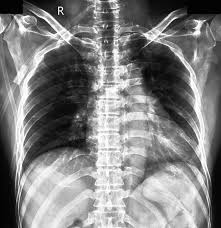

Q1: 갈비뼈 금은 X-ray에서 안 보일 수도 있나요?

A1: 네, 초기에는 X-ray에서 잘 보이지 않는 경우도 있어 증상과 촉진이 중요합니다.